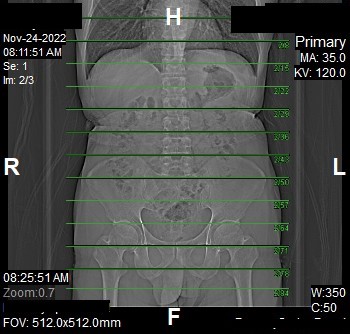

Topogram

- Position the patient in head first supine position.

- Align the patient in Mid-Sagittal plane of the table.

- Position the transverse laser light beam at the level of patient’s nipple line to start the topogram.

Topogram Parameters

- Topogram length: 512 mm

- Slice: 0.6 mm

- Scanning direction: Craniocoudal

- Tube position: Top

- Stop the topogram scanning when the scanning reach / pass over the inferior ischial ramus.